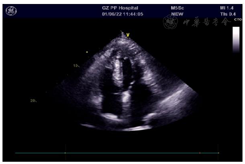

影像学检查:肺部CT示双肺散在慢性炎症和右肺上叶陈旧性结核灶,心脏彩超提示双房增大,左室壁心尖段肥厚,二尖瓣、三尖瓣轻度反流,大量心包积液(图1)。